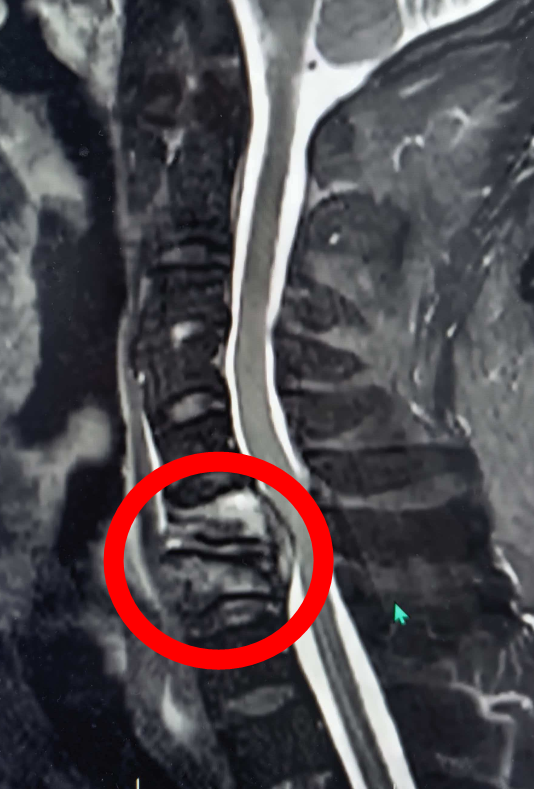

9个月前,刘先生突发颈肩部及双上肢疼痛,逐渐出现双下肢麻木、无力,行走困难,双下肢不完全瘫痪,每日备受折磨,当地医院予以相关检查显示其颈6-7椎体骨质破坏,颈椎不稳,考虑感染性病变,还伴随椎管内脓肿、脓肿压迫导致脊髓神经损伤,若不及时手术,随时可能下肢完全瘫痪。

为给患者争取生机,科室迅速启动全院多学科会诊,联合心血管内科、麻醉科、呼吸科、临床药学、重症医学科等专家反复评估。心内科专家指导术前心功能优化,麻醉科专家制定术中循环监测与应急方案,脊柱外科团队则选择创伤更小、恢复更快的颈椎前路手术方式,直接清除颈椎前方的病灶,重建脊柱稳定性,最大限度降低对心脏的负荷。

2025年12月17日,在全身麻醉下,脊柱外科主任王炯团队凭借精湛技术,顺利完成颈椎前路融合术+病灶清除+椎管减压+内固定术,全程避开神经与血管,仅用1.5小时完成手术,术中出血量50ml,远超预期。术后患者转入重症监护室,在多学科团队协同治疗下,病情稳定好转。